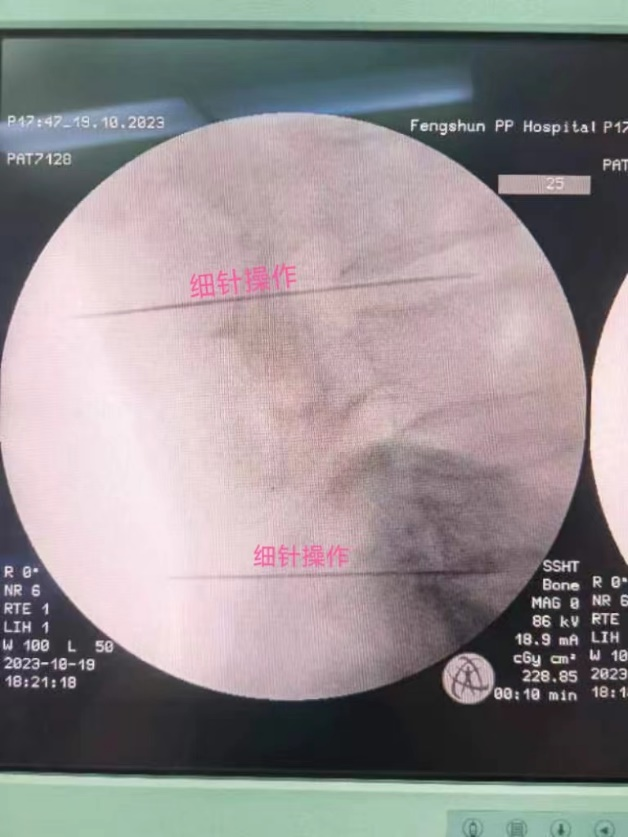

丰顺县人民医院麻醉疼痛诊疗中心2023年7月份引进德国进口临床臭氧治疗仪至今,已常规开展腰椎间盘臭氧消融术数十例,凭借一根“细针”,在C臂X光机的指引下,将适量的臭氧气体注射到病变椎间盘髓核,达到消融固缩突出椎间盘,解除脊神经压迫疼痛的治疗效果,操作快速简便,微创且恢复快,凭借出色的疗效,深受广大患者好评!

▲ 精准定位